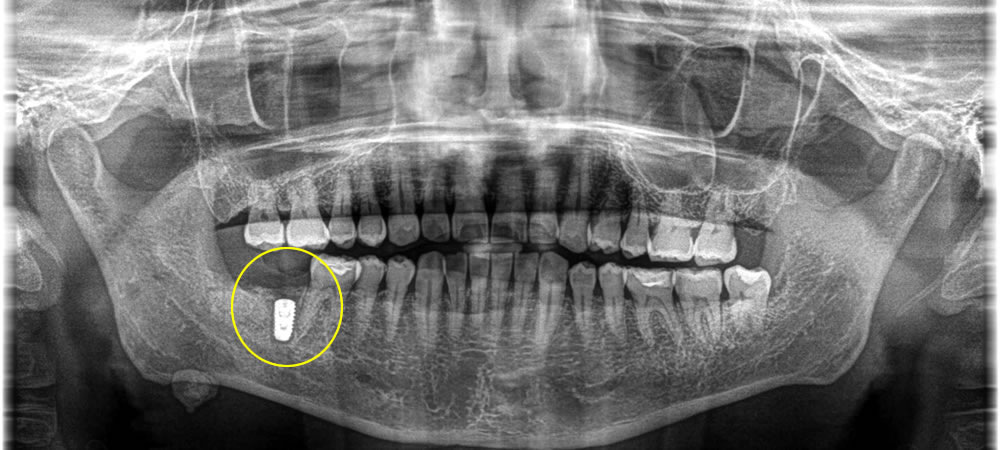

上部構造の装着・治療完了

埋入したインプラントと顎骨がしっかりと結合していることを確認後、製作した上部構造(ジルコニアクラウン)を装着し、咬み合わせを調整して治療完了となりました。

術後は奥歯で硬いものもしっかりと噛むことができるようになりました。また、親知らずを抜歯したことによって清掃性も良くなり、口腔内の環境も改善しました。